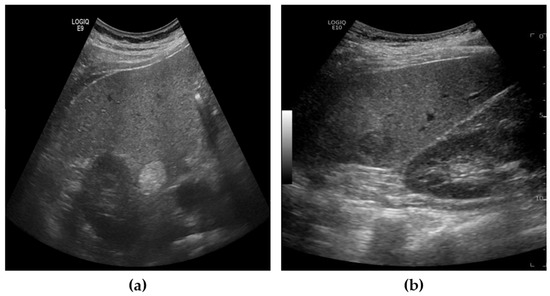

3.3. Performance of Lesion Classification

The lesions identified through SM-WBF were classified using a CNN. Among various models, we selected EfficientNet-b0, known for its efficiency and performance, for comparison. As shown in Figure 8, the lesions were classified into three classes: benign, malignant, and error. For training, the image size was resized to 300 × 300, and the input size of EfficientNet-b0 was modified from its default 224 × 224 to 300 × 300. This adjustment was made to ensure accurate classification, as reducing the image size excessively could compromise the model’s performance.

Figure 8. The lesions were classified into three classes using EfficientNet-b0.